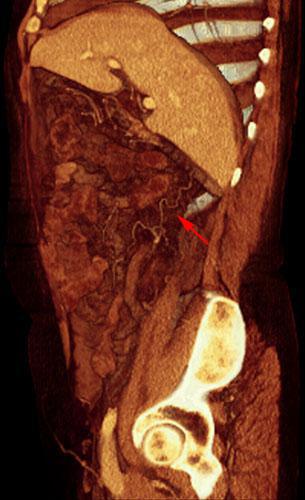

Nefrectomía radical